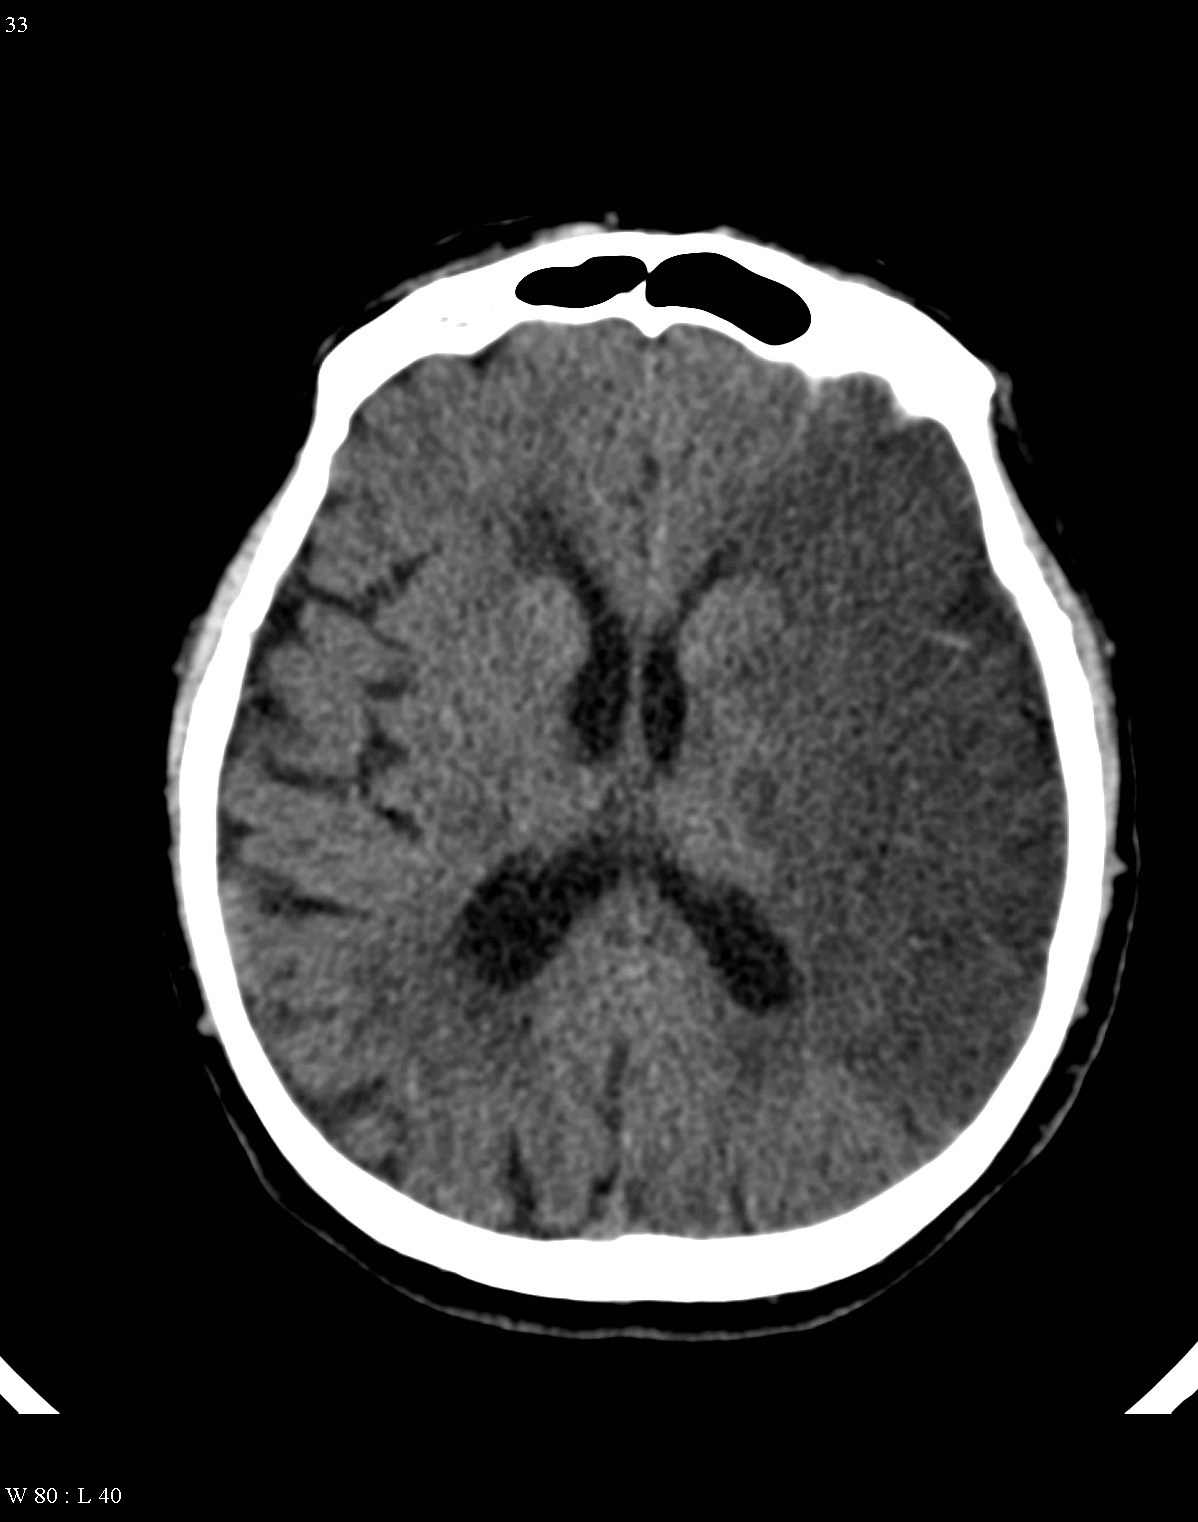

In acute phase (12-24 hours after the occlusion of the middle cerebral artery) on CT hypodense basal ganglia, the loss of cortical white-grey matter differentiation and sulcal effacement are the characteristic imaging findings.

In the chronic phase of the infarct (months to years) the hypodensity of the lesion (CT) reaches the level of the cerebrospinal fluid. There is no more contrast enhancement, the lesion is well differentiated and it degenerates into a cyst secondary to encephalomalacia. The brain parenchyma experiences a volume decrease due to the degeneration (sometimes calcifications can occur at the marginal border of the infarct).